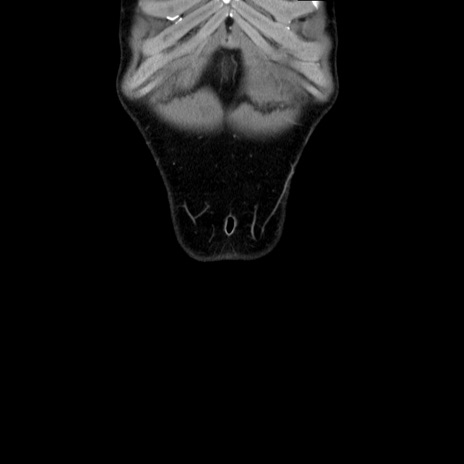

症例36(冠状断像)

【症例】20歳代 男性

【主訴】心窩部痛

【現病歴】今朝より上腹部痛あり。一旦軽快していたが再度出現したため救急要請。昨日夕に白身の魚を含む刺身を食べた。

【身体所見】BP 136/89mmHg、HR 74/min、BT 37.0℃、腹部:膨満、軟、心窩部に圧痛あり。反跳痛なし、筋性防御なし、腸雑音やや亢進あり。

【データ】WBC 17700、CRP 0.48